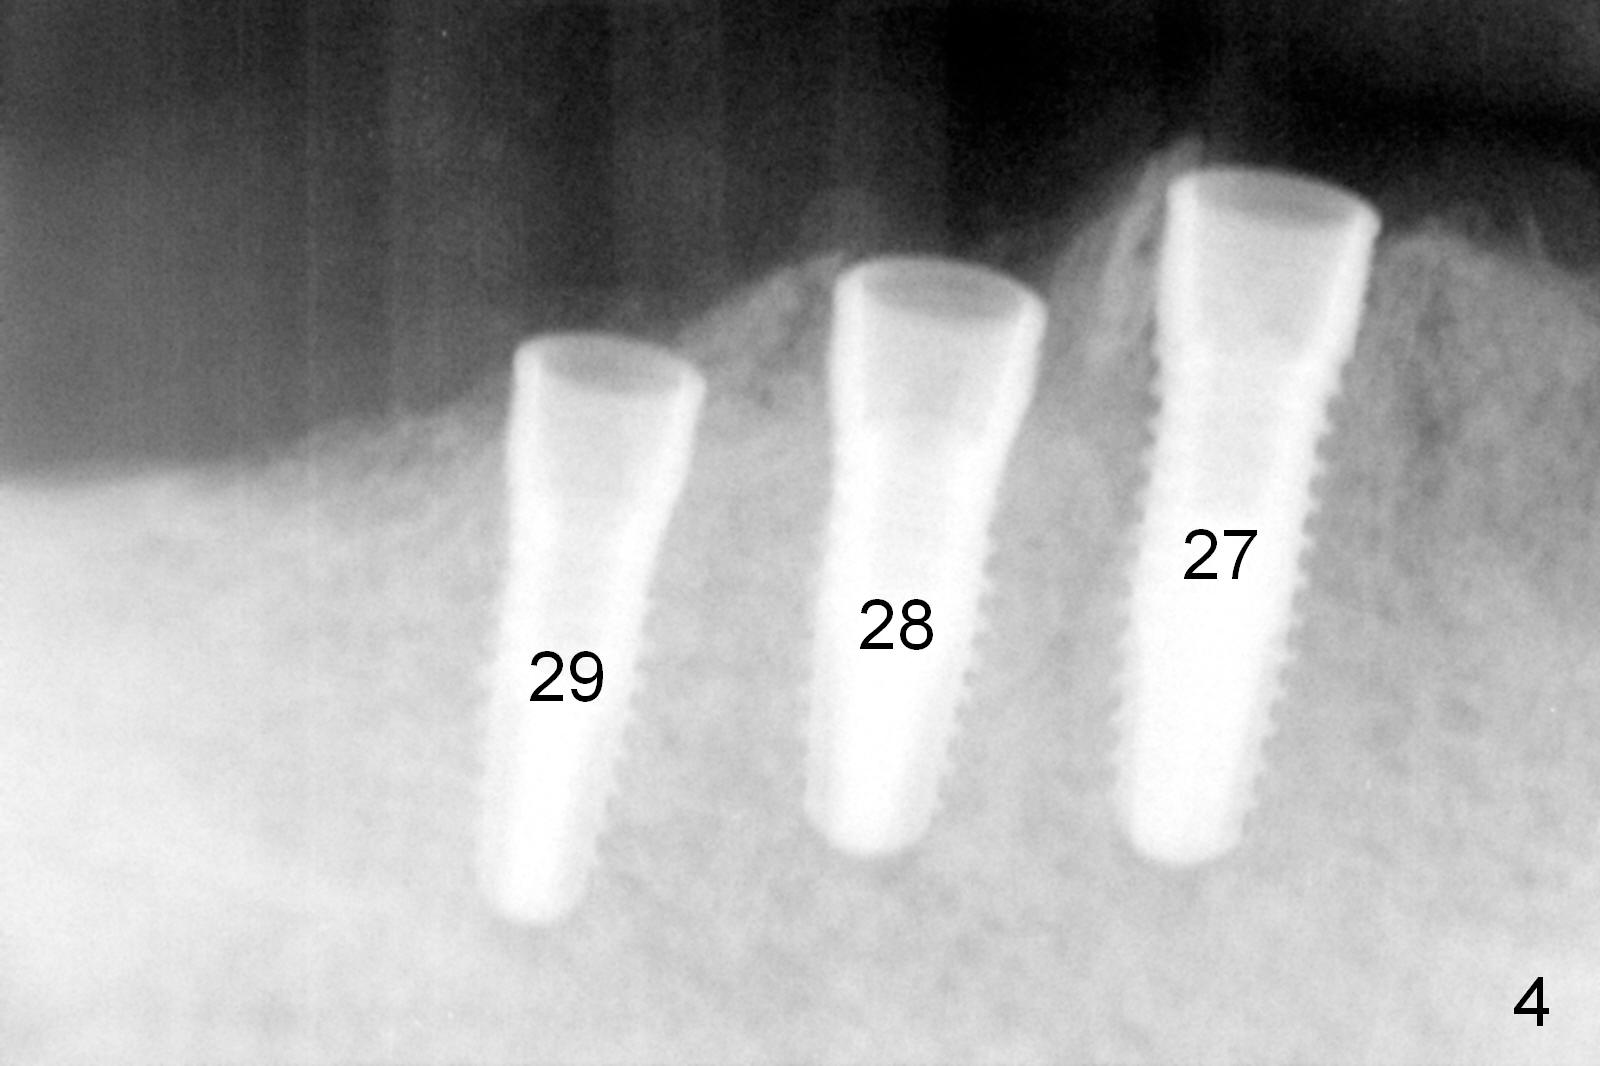

A 86-year-old man returns to office for the lower right quadrant reconstruction with implants. In addition to the immediate ones at the sites of #27 and 28 (Fig.1), how many and where else? The patient reveals that he does not plan to get an implant at the site of #3 (Fig.2). Therefore there is no need for an implant at #30. Preop CT shows that bone width is compromised at #26. So the 3rd site will be #29 (Fig.3,4). All of the 3 implants (4.5x14 mm, 4.5x12, and 4.1x12 mm) achieve primary stability (»55 Ncm). An immediate provisional could be provided, but it seems difficult to close the buccal (Fig.5 B) gaps of #27 and 28 after bone graft with the provisional. In contrast, the gingiva adapts to the implant at #29 well (Fig.6 B). Perio dressing is applied to the abutments (Fig. 7: #27-29), the edentulous space at #26 and the neighboring teeth (#23,24). It would be ideal to apply a non-resorbable membrane to the buccal opening at #27,28 (Fig.8 white line) prior to perio dressing placement. In case of dislodgement of the latter, the membrane is able to keep bone graft in place.